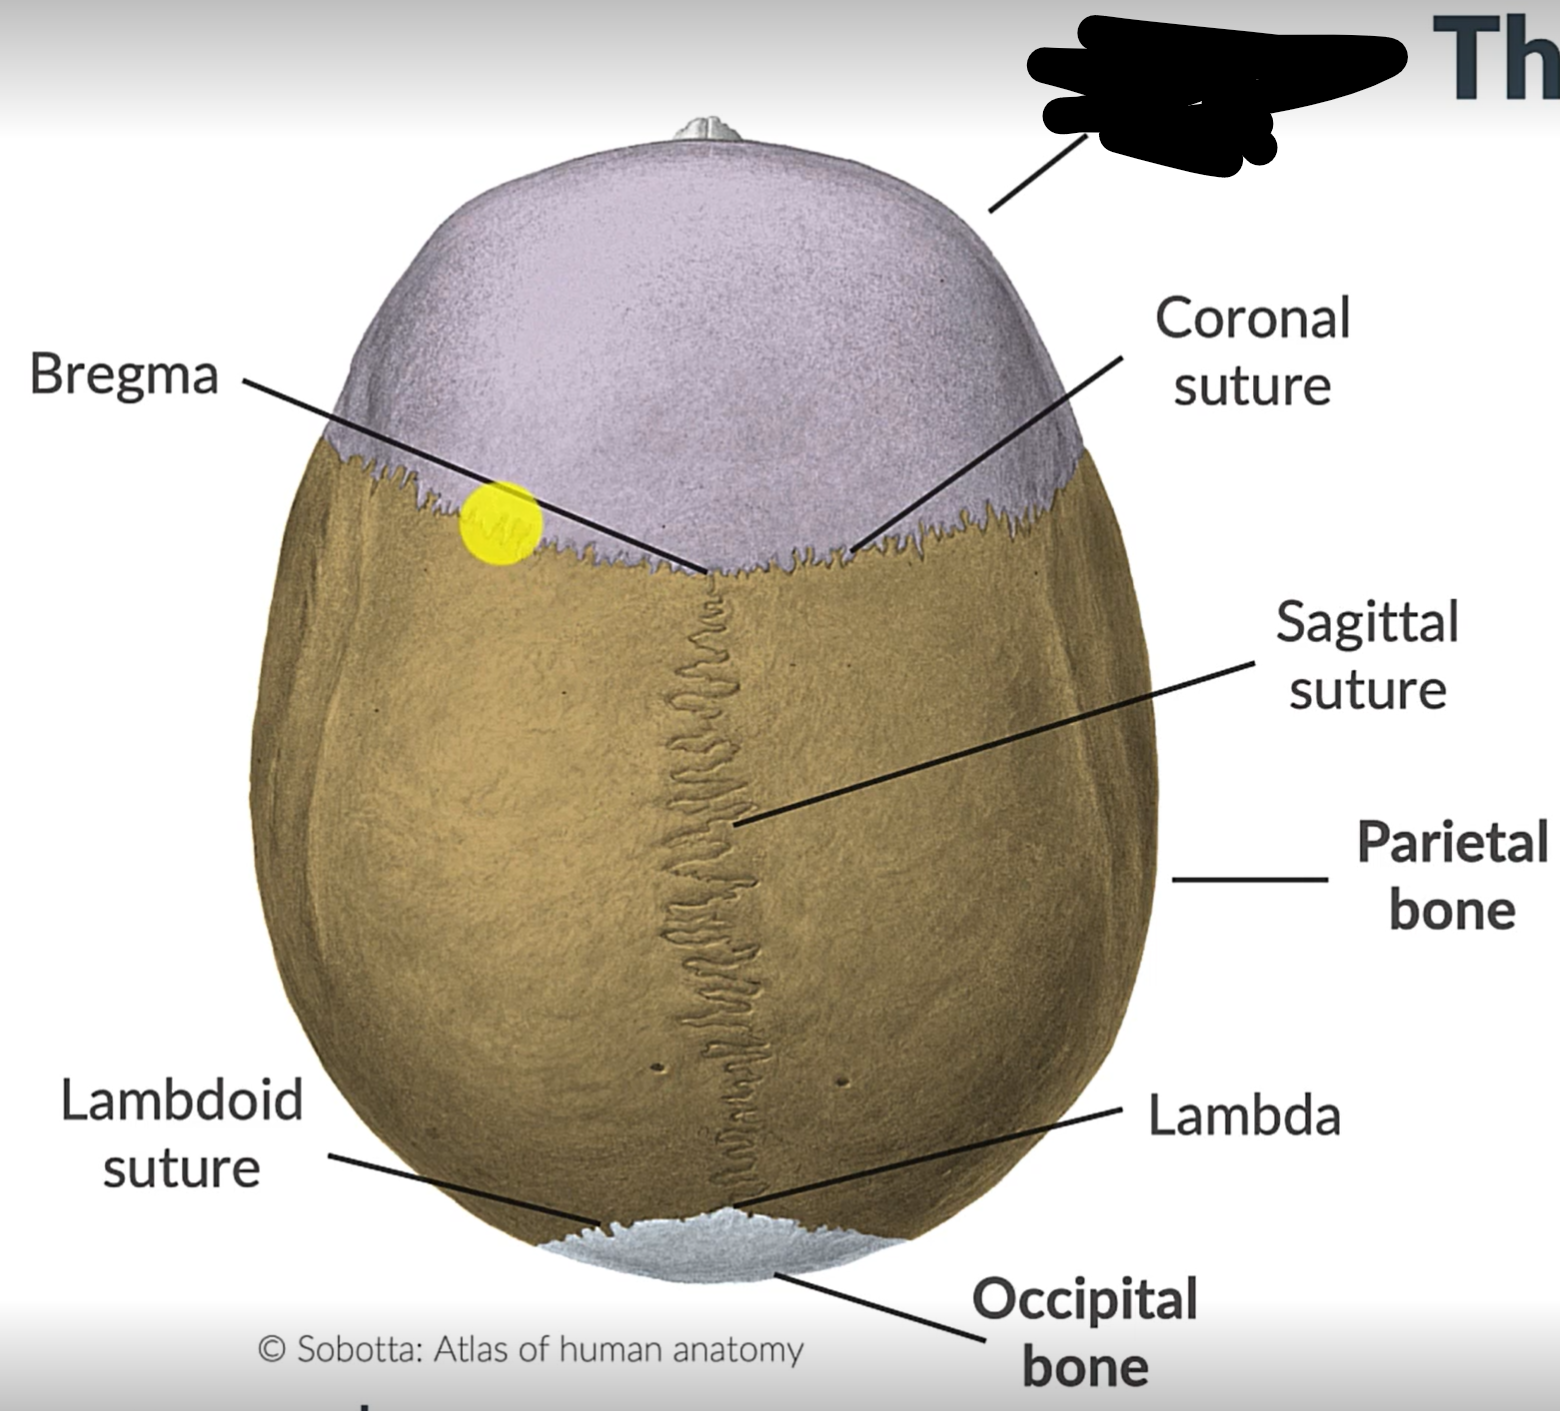

What are the 4 cranial sutures and what do they separate?

Lambdoid - separates occipital from parietal and temporal

Sagittal - extends between parietal bones

Coronal - divides frontal and parietal bones

Squamous - either side of cranium, separates temporal and parietal bones

Sagittal suture

Lambdoid suture

Occipital bone

What is the point where the frontal and parietal bones meet?

Bregma

Lambda